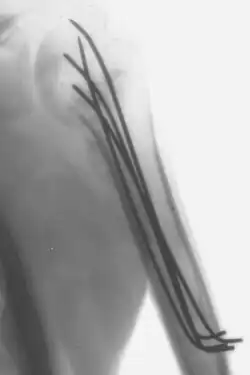

Drut Kirschnera

Drut Kirschnera (ang. Kirschner wire, K wire, K pin) – cienki i sztywny drut używany do stabilizacji odłamów kostnych. Mogą być one mocowane w kości przezskórnie, co niekiedy pozwala uniknąć bardziej inwazyjnych zabiegów. Niekiedy stosuje się je jako samodzielne wewnętrzne stabilizatory, innym zaś razem jako element bardziej skomplikowanych stabilizatorów np. aparatu Ilizarowa. Stosowany także przy wyciągu bezpośrednim.